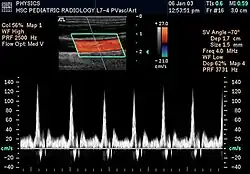

L'échographie Doppler est un examen médical échographique en deux dimensions non invasif qui permet d'explorer les flux sanguins intracardiaques et intravasculaires. Elle est basée sur un phénomène physique des ultrasons : l'effet Doppler. Elle est souvent surnommée écho Doppler.

En pratique médicale l'échographie Doppler est utilisée pour explorer le réseau artériel et le réseau veineux afin d'évaluer certaines affections : thrombose veineuse profonde (phlébite), varices, artériopathie, thromboses, anévrismes, etc.

L’échographe Doppler est constitué d’un échographe classique couplé à une sonde Doppler.

Lorsqu'un faisceau d'ultrasons traverse les cavités cardiaques ou les vaisseaux, l’écho renvoyé par les éléments figurés du sang (qui deviennent des émetteurs) aura une longueur d'onde plus longue (son plus grave) s'ils s'éloignent du capteur ; et une longueur d'onde plus courte (son plus aigu) s'ils se dirigent vers le capteur.

La sonde Doppler recueillera donc un écho dont la fréquence (longueur d'onde) sera différente de la fréquence d'émission.

La différence des fréquences d'émission (F) et de réception (F'), F - F', permet de calculer la vitesse et la direction des globules rouges.

Les échographes Doppler actuels permettent un codage couleur des flux sanguins. Par convention, les flux positifs qui s'approchent de la sonde sont codés en rouge, les flux qui s'en éloignent sont codés en bleu. Il permet ainsi une visualisation directe des flux sanguins qui se superposent à l'image en échographie bidimensionnelle en échelle de gris.